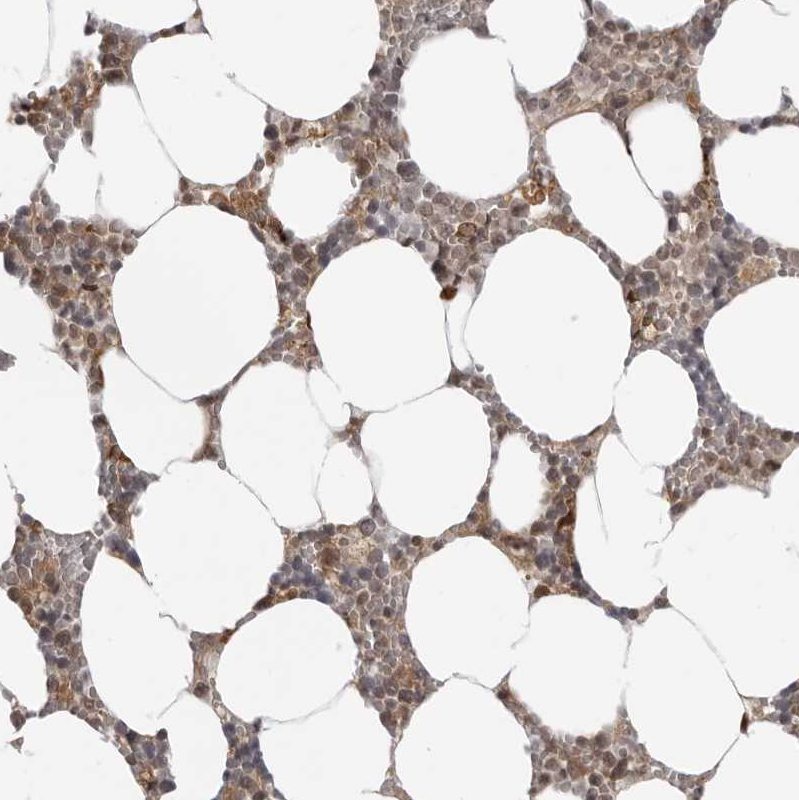

Immunohistochemical staining of human Cerebral cortex shows moderate nuclear positivity in glial cells.